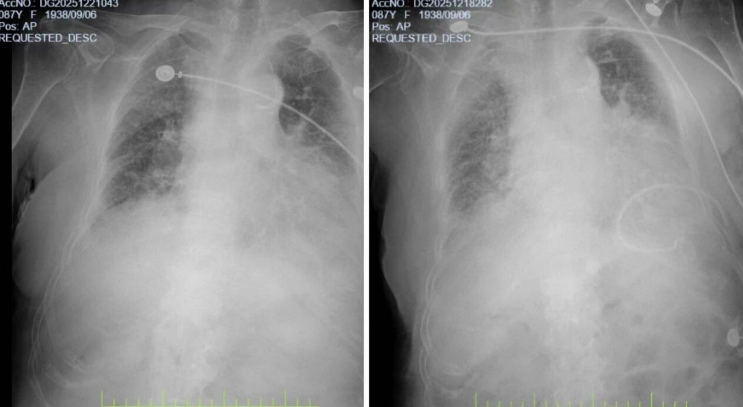

*胸部DR影像图

在ICU期间,医护团队全力开展呼吸支持、强心利尿、控制感染等抢救措施,精准处置肺水肿,逐步稳定患者生命体征。待病情平稳后,患者转入呼吸内科病区继续治疗。此时,老人仍面临重症肺炎、Ⅱ型呼吸衰竭、心肌损伤、心功能不全等多重挑战,肺部炎症广泛,肝肾功能、电解质紊乱等问题亟待解决。

经过接力救治与精心护理,患者咳嗽、气促症状明显缓解,肺水肿消退,肺部炎症范围缩小,感染指标恢复正常,心、肾等器官功能稳定。复查胸部CT显示双肺病变较前明显吸收,患者顺利康复出院,家属表示真诚的感谢,并送上锦旗。